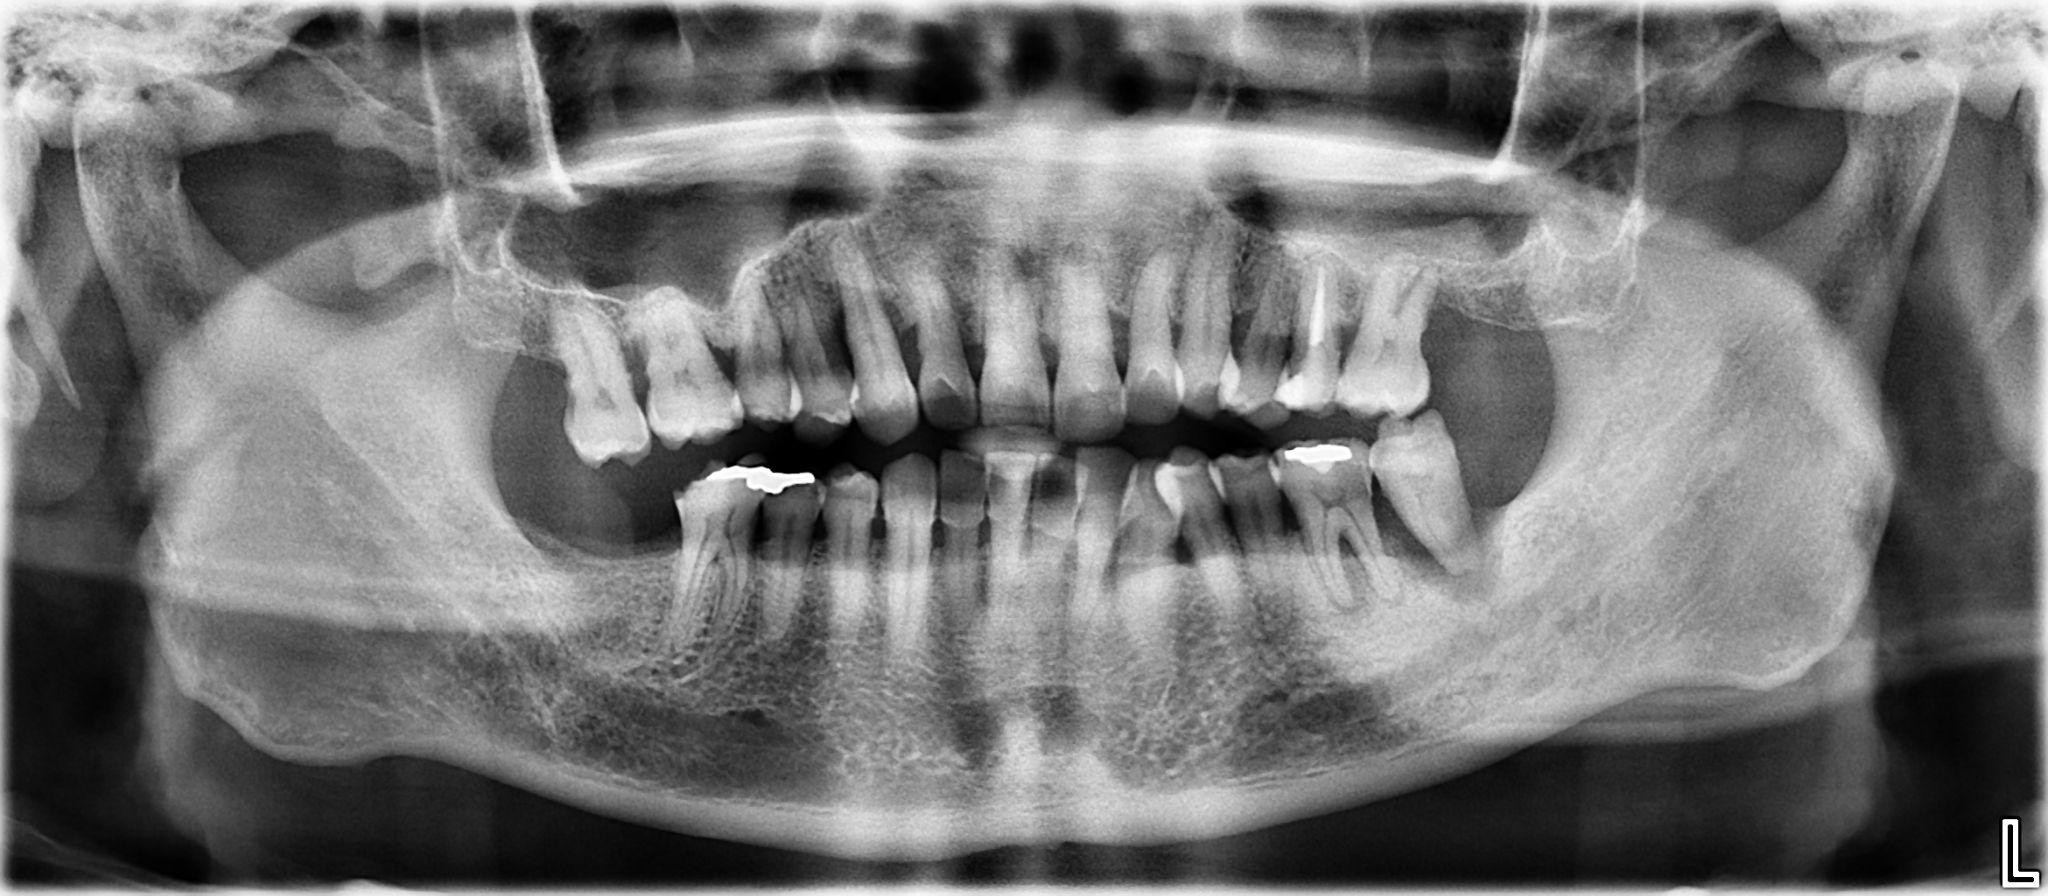

5. What options can be selected for the first quadrant of this panoramic X ray?

6. What options can be selected for the second quadrant of this panoramic X ray?

7. What options can be selected for the third quadrant of this panoramic X ray?

8. What options can be selected for the forth quadrant of this panoramic X ray?